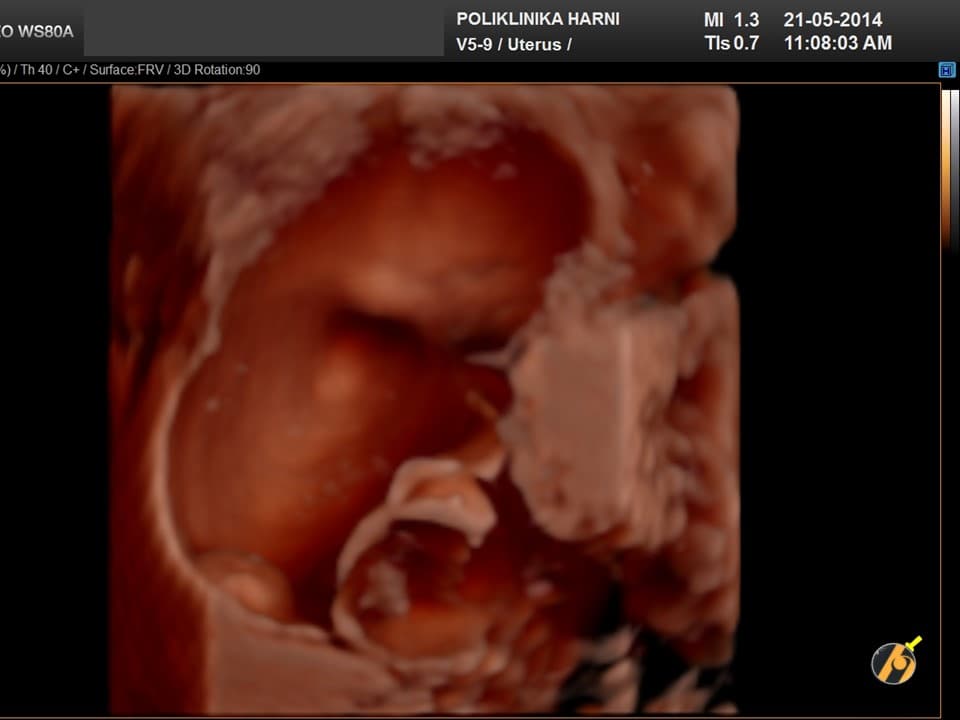

Nažalost, još uvijek ne postoji znanstveno potvrđena dijagnostička metoda koja bi se mogla nazvati metodom probira za karcinom jajnika. Za rano otkriće raka jajnika nužne su i veoma važne redovite ginekološke kontrole uz vaginalni ultrazvuk, odnosno pregled vaginalnim color-Doppler ultrazvukom. U slučaju nejasnih nalaza, uz standardnu laboratorijsku obradu određuju se tumorski biljezi. Optimalni tumorski biljeg za serozne karcinome koji se najčešće javljaju je CA 125, kod rjeđih mucinozni varijanti su to CEA i CA 19-9, a kod endometrioidnih i mucinoznih karcinoma AFP, te ß-hCG kod embrionalnih i koriokarcinoma. U novije vrijeme tumorskim biljezima za rak jajnika su pridodani HE-4 i ROMA indeks.